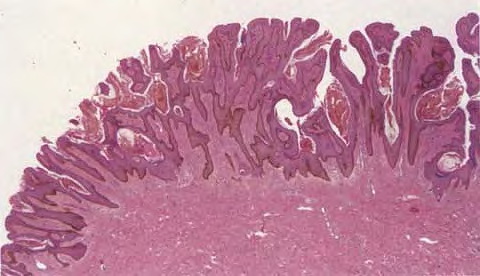

Epidermal naevus = الوحمة البشروية